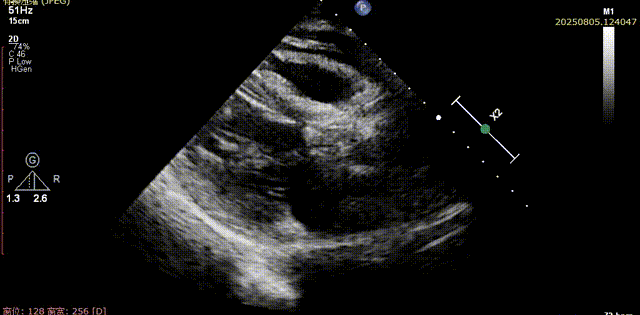

体外量取工作距离,猪尾置入窦底,交换加硬导丝,加硬导丝支撑下缓慢置入大鞘。大鞘置入后,经加硬导丝导入AL导管,采用150cm直头导丝跨瓣,超声下可见导丝顺利通过瓣口,将AL导入左室,交换预塑形加硬导丝

直头导丝跨瓣

AL导管送入左室

加硬导丝送入左室

心尖切面确认导丝位置